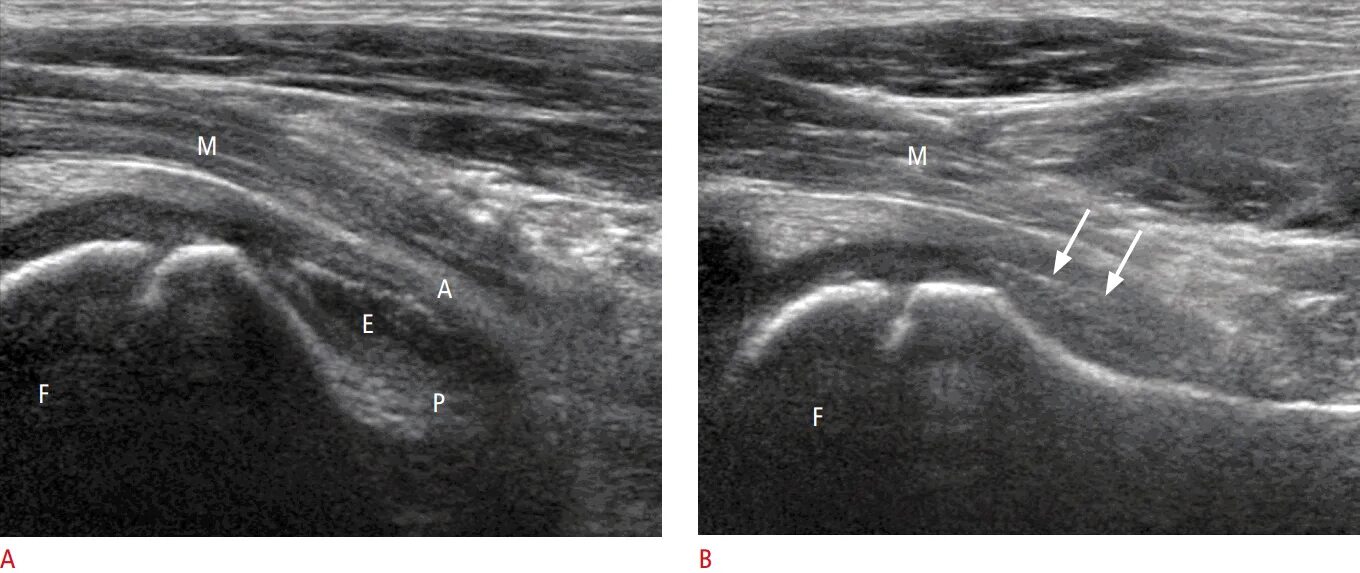

Где сделать узи тазобедренного сустава